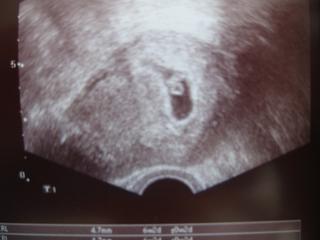

@simonkazga Ja som tiež nevedela zaspať. Bola som v CAR, lebo my sme mali IUI, a tam ten ultrazvuk nie je nic moc, navyše som čakala hodinu, lebo lekárka mala nejakú súrnu operáciu, tak sa potom ponáhľala a len sucho skonštatovala, že všetko je v poriadku, vidi srdečnú akciu a mám prísť o 3 týždne. Až som zostala taka obarená, že aj tešiť som sa zabudla. Ale už mi to postupne dochádza 🙂 Držím veľmi palce!

@matulienka.d Som 6tt+1, nepočuli sme, ale lekárka videla. Ja som na tom monitore vela nevidela.

Ahojte, tak dnes návšteva u lekára na jednotku, drobček má 0,61cm, akcia srdiečka bola...tehotenská knižka vypísaná, ďalšiu poradňu a odber krvi budem mať 15.06. Ešte mi stihol spraviť aj cytologiu. A termín pôrodu mi zmenil z 1.1. na 2.1. ale ked to bude ako Tomáško o pár dní skôr tak to bude ešte decembrové. Ved uvidíme

ahojte, tak ja to mám tiež potvrdené od dr., termín mi stanovil zatiaľ podľa sona na 11.1., akcia srdiečka bola tak som rada 😉 21.6. idem na všetky odbery a tehu knižku ak bude všetko v poriadku /klop, klop, klop/ 🙂

tak dnes som aj ja bola u dokiho...podla sona mi povedal,ze to vyzera na 5-6 tt..... ale ze viac po sone o 3 tt, takze sa k Vam velmi rada pridam a podelim sa s Vami o priebeh tehu a spolocne s Vami sa bude tesit na malicke mimi...Tak vsetkym este raz zelam hlavne vela vela zdravia 🙂